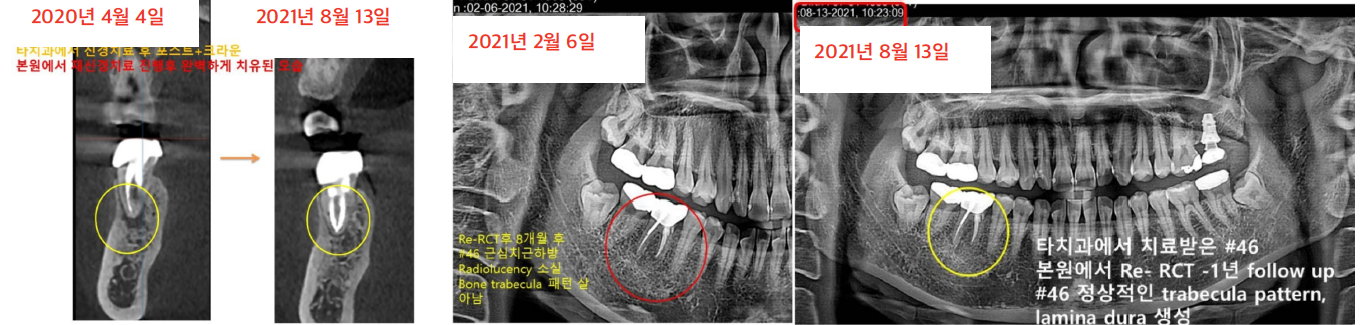

수많은 임플란트 케이스를 진행하면서도 이백점치과는 '자연치아는 그 어떤 임플란트로도 대체할 수 없다'는 확고한 철학을 가지고 있습니다. 그래서 언제나 자연치아를 살리기 위해 최선을 다합니다. 이번 사례는 타 치과에서 발치 진단을 받은 치아를 성공적으로 재신경치료하여 살려낸 고난도 케이스입니다. CASE. "뽑아야 한다던 치아, 재신경치료로 살려냈어요!" ○환자분의 고민 - 타 치과에서 이미 신경치료를 받았음에도 계속 불편감을 호소하며 내원한 환자분이었습니다. - 오른쪽 아래 치아 앞 잇몸에 고름 주머니(농양)가 생겨 있었고,  방사선 사진상 뿌리 끝에 심한 염증과 고름이 확인되었습니다. - 더욱이 이미 신경치료 후 포스트(기둥)까지 박혀있어, 타 치과에서는 이미 '발치'를 고지받은 상황이었습니다. ![]() ○ 진단: 정밀 CT 촬영을 통해 고름 주머니가 생긴 원인을 분석했습니다. 기존 신경치료가 되어있던 뒤쪽 뿌리가 아닌,  앞쪽 뿌리의 신경관에 문제가 발생하여 염증이 재발된 것을 정확히 진단했습니다. ![]() '발치 없이' 자연치아를 살리는 재신경치료 이백점치과는 고심 끝에 기존 기둥을 그대로 두고, 문제의 원인이었던 앞쪽 뿌리를 다시 신경치료하기로 결정했습니다. 1. 정교한 기존 재료 제거 : 기존에 충전되어 있던 신경치료 재료를 조심스럽게 제거했습니다. 2. 꼼꼼한 신경관 재정비 : 뿌리 끝까지 신경관을 깨끗하게 넓히고 소독했습니다. 3. 염증 해소 약재 적용 : 뿌리 끝 염증 해소를 위해 염증 완화 약재를 세심하게 적용했습니다. 기적 같은 결과, 1년 후에도 건강하게! - 3주 만의 드라마틱한 호전: 불과 3주 만에 바깥 잇몸의 고름 주머니가 완전히 없어졌고, 환자분의 모든 증상이 사라졌습니다.  이후 신경치료를 마무리하고 보철 치료까지 성공적으로 진행했습니다. - 1년 뒤에도 완벽한 경과: 1년 뒤 다시 체크했을 때, 염증은 전부 가라앉았고 고름 주머니 흔적 없이 깨끗했습니다.  심지어 염증으로 녹아있던 뼈 부위에는 새로운 뼈가 형성되고 있음이 확인되었습니다. ![]() 환자분 또한 통증 없이 건강하게 생활할 수 있어 매우 감사하다는 인사를 전했습니다. ![]() 이처럼 살리기 어렵다고 판단되던 고난도 치아를 발치 없이 살려낸 사례는 의료계 내부에서도 높은 평가를 받았습 니다. 이백점치과는 항상 환자분의 입장에서 생각하며 '발치만이 해답이 아님'을 증명하고, 자연치아 보존을 위한 최선의 노력을 다하고 있습니다. ![]()  |